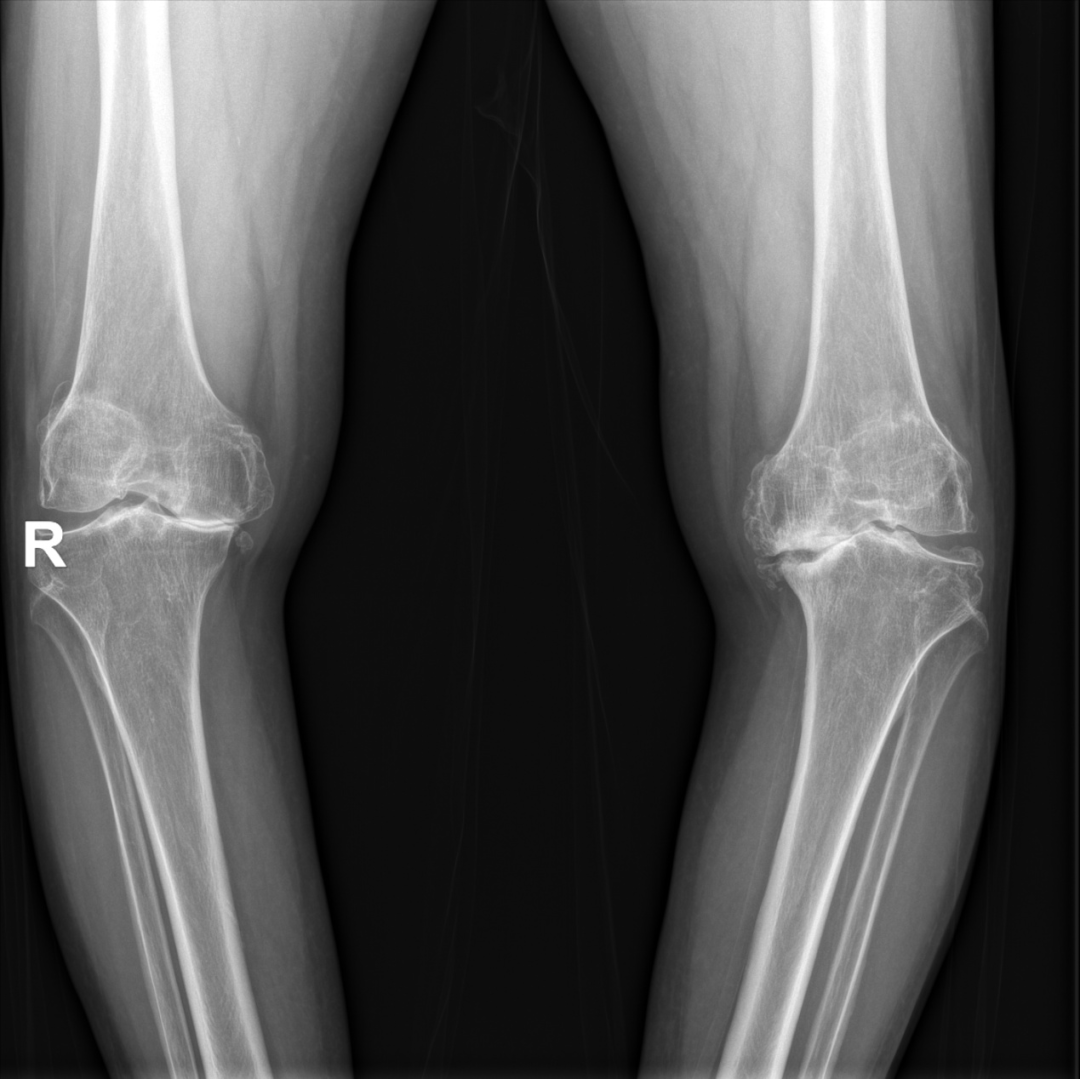

徐驰主任根据患者病情,结合查体、影像学检查,认为只有实施手术治疗才能改善患者的行走功能,提高患者的生活质量。团队制定了详细的手术方案,患者目前最核心的问题是双侧膝关节疼痛、行走严重障碍,双侧膝关节屈伸功能明显受限,可行双侧人工膝关节表面置换术,以人工关节替代损毁关节,重建结构,恢复功能。但由于秦女士为高龄患者,膝关节功能严重障碍,畸形明显,且合并多种内科疾病,手术难度较大、时间较长,为了降低手术风险,决定分两次对秦女士进行人工膝关节表面置换术。

双膝关节内翻畸形